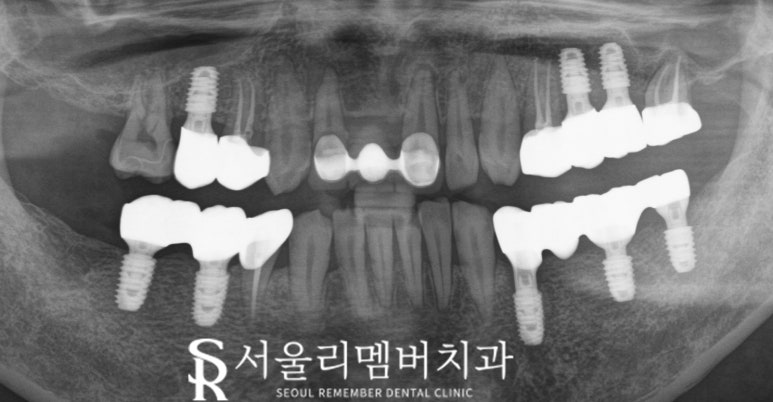

앞선 진단을 통해 계획을 세웠는데요,

총 여섯 개의 발치와 여덟 개의 임플란트 식립,

그리고 네 개의 근관제거술을

진행하는 것이 좋겠습니다.

최종 결과

마지막으로 임플란트에 보철물을 올려

모든 진료를 끝마칠 수 있는데요,